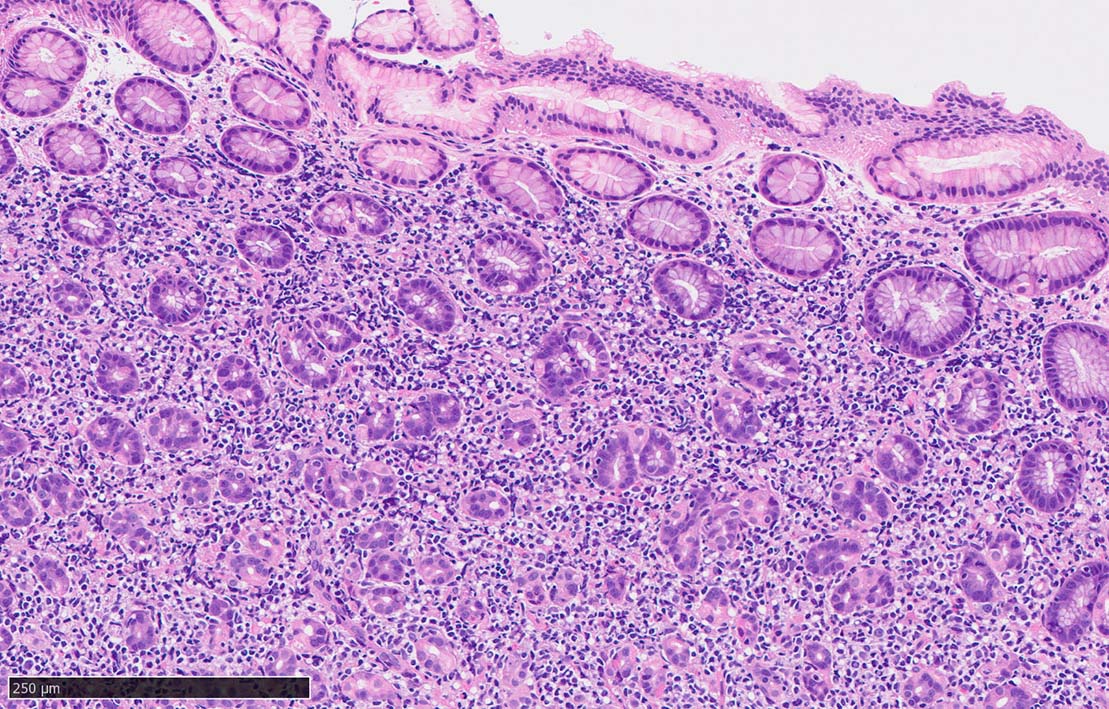

60 year-old male. 胃生検組織

stomach biopsy, HE

x200

非結節部位

固有腺のLEL様所見